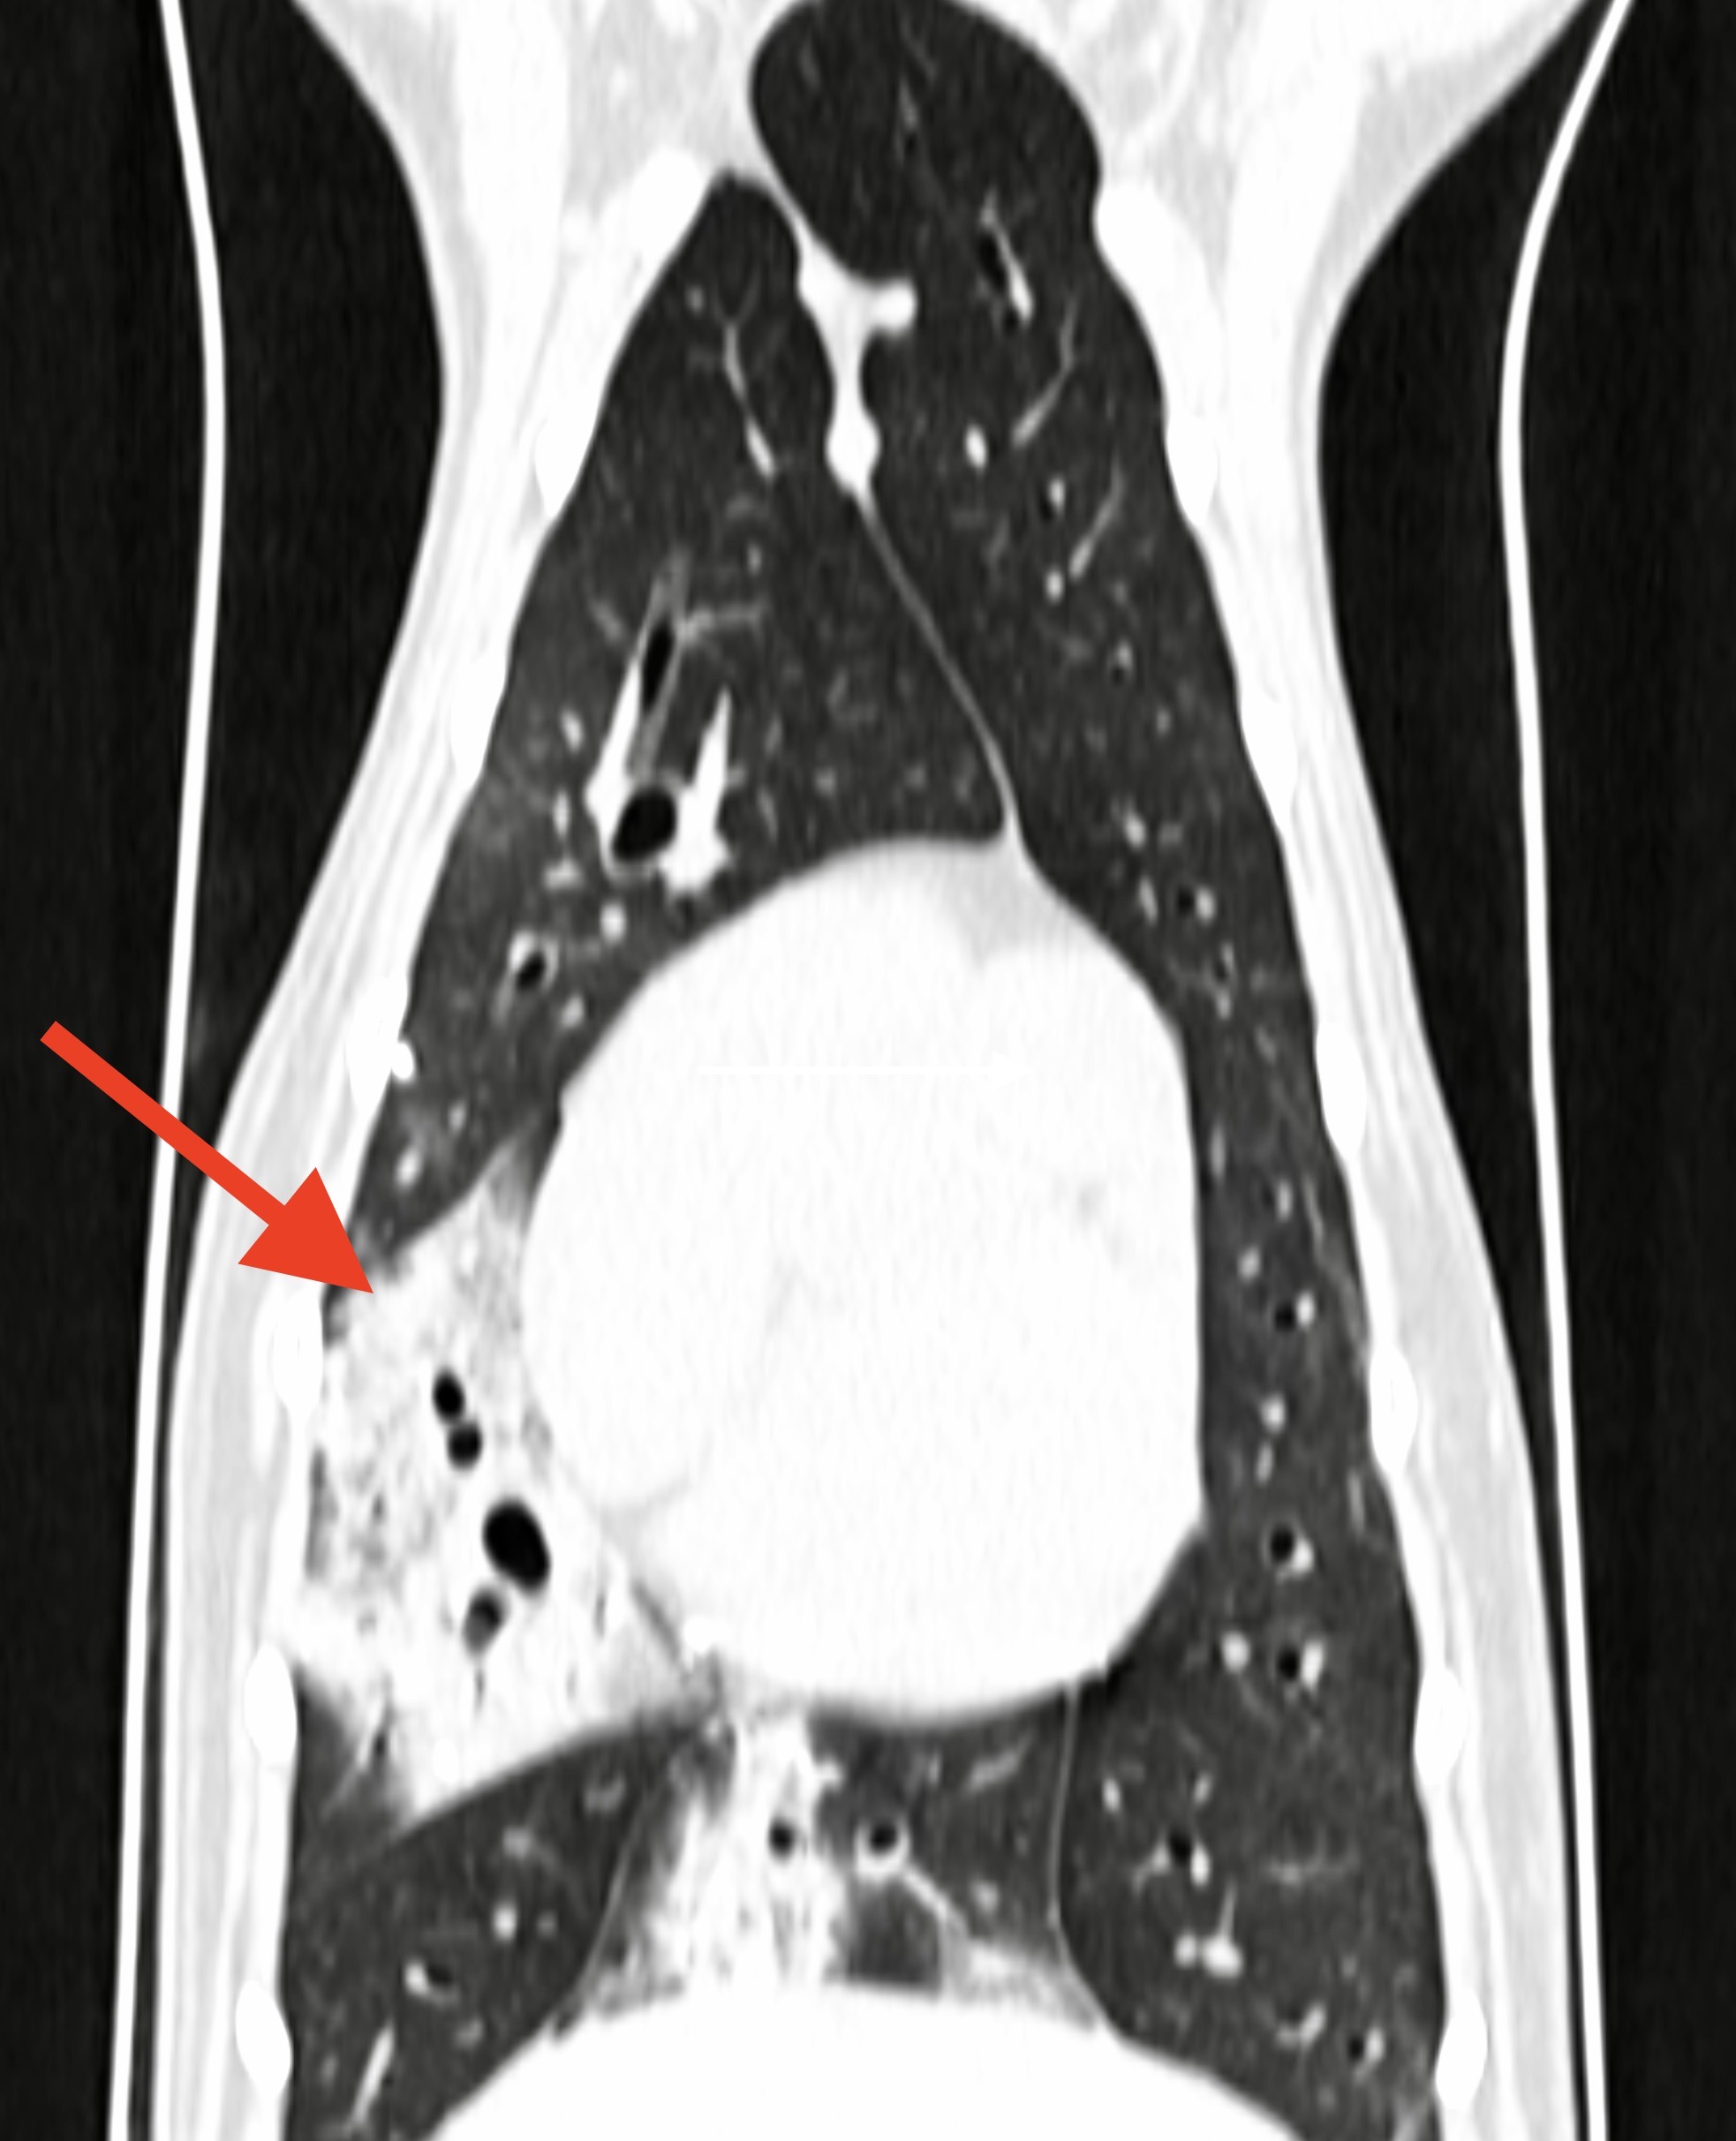

Scanner pulmonaire chez deux chiennes : à gauche, consolidation de la partie ventrale des lobes pulmonaires moyen droit et accessoire, compatible avec une pneumonie par fausse déglutition, chez une border collie atteinte de paralysie laryngée. A droite : Deux métastases pulmonaires chez une chienne présentant un carcinome mammaire de grade 3 (autrement dit, une tumeur mammaire très méchante).